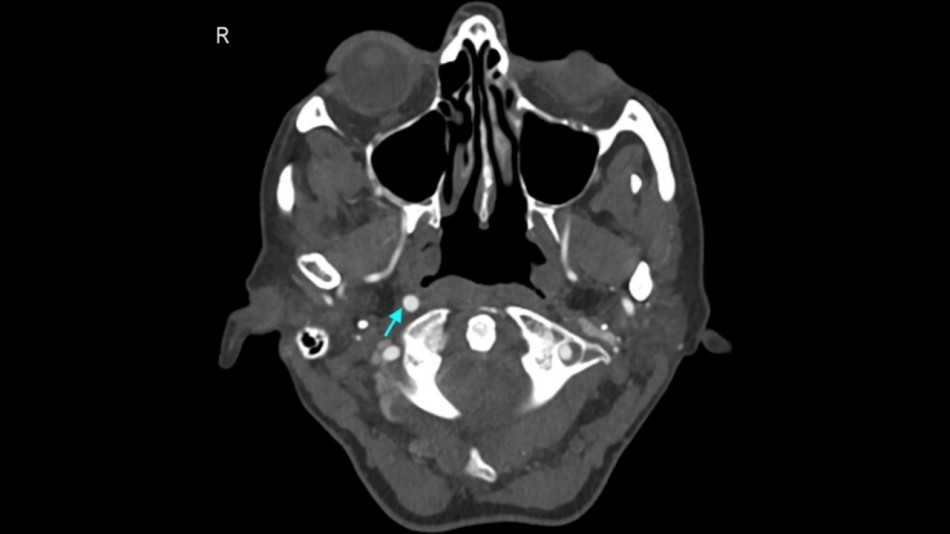

Нервові клітини. Lindsay Cameron / UC Davis